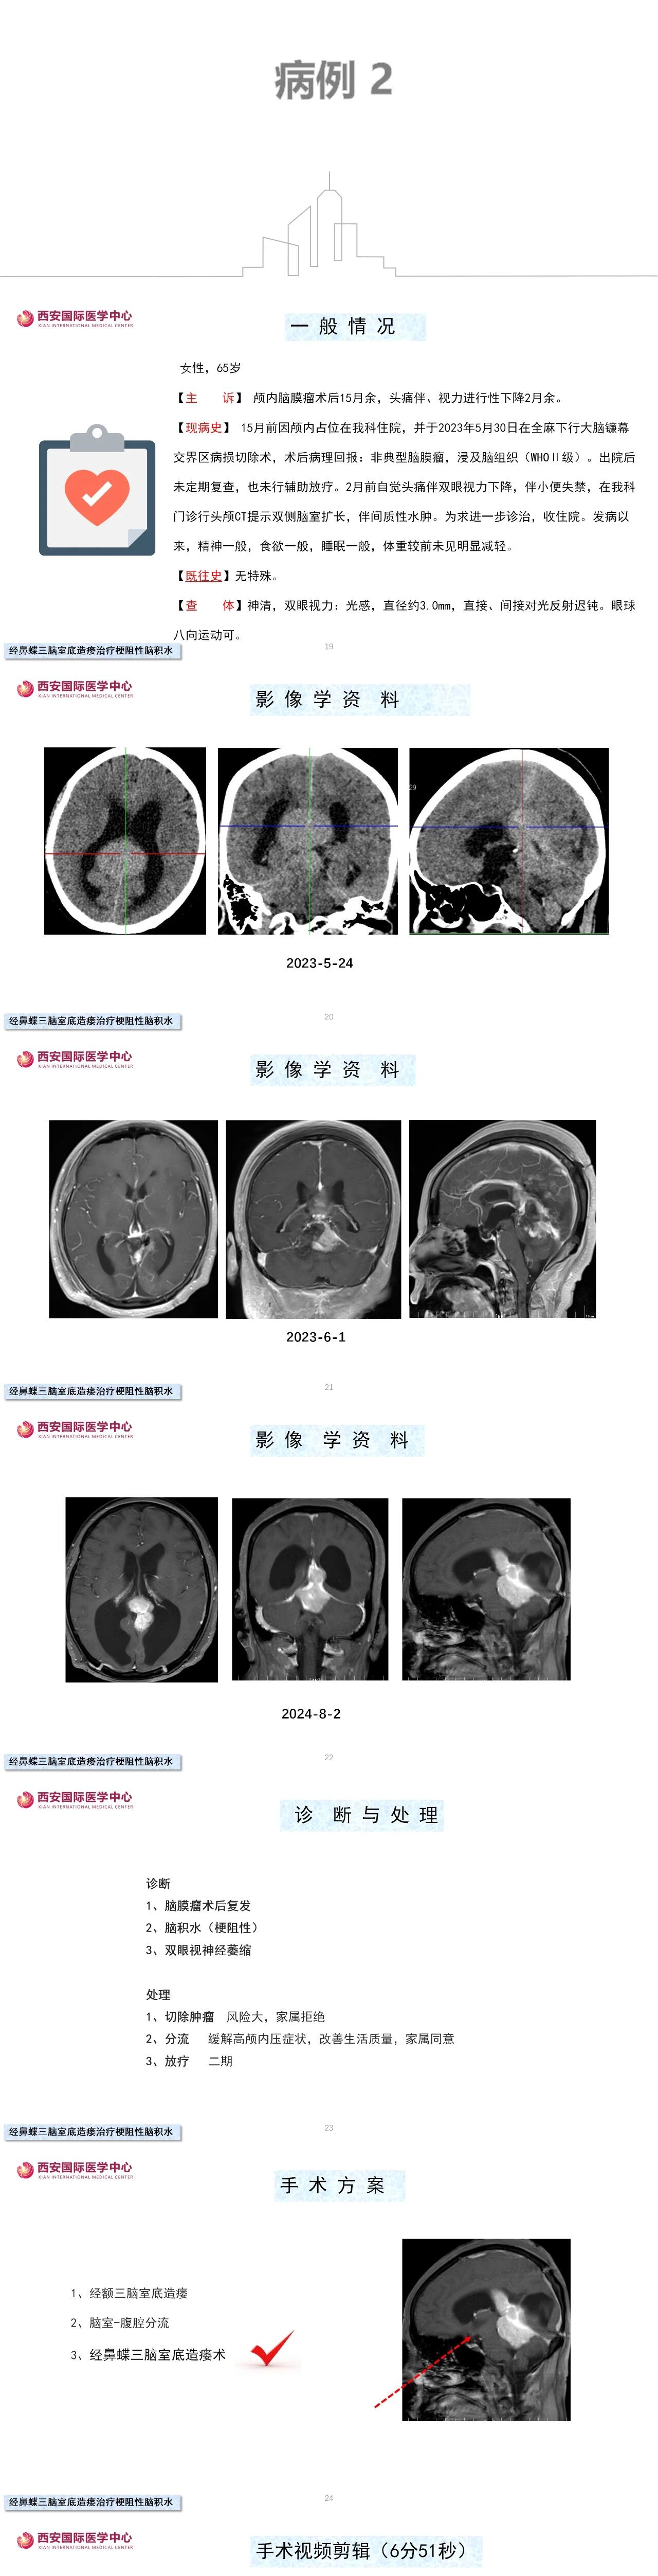

第三脑室底造瘘术是梗阻性脑积水公认的首选治疗方式。随着显微镜、内镜技术的发展,以及微创理念的不断更新,从传统的经额叶皮层入路逐渐转变为经纵裂胼胝体入路,再到我们独创的神经内镜经鼻蝶第三脑室底造瘘术,可谓将微创理念发挥到极致,对脑组织几乎无损伤,手术效果满意。